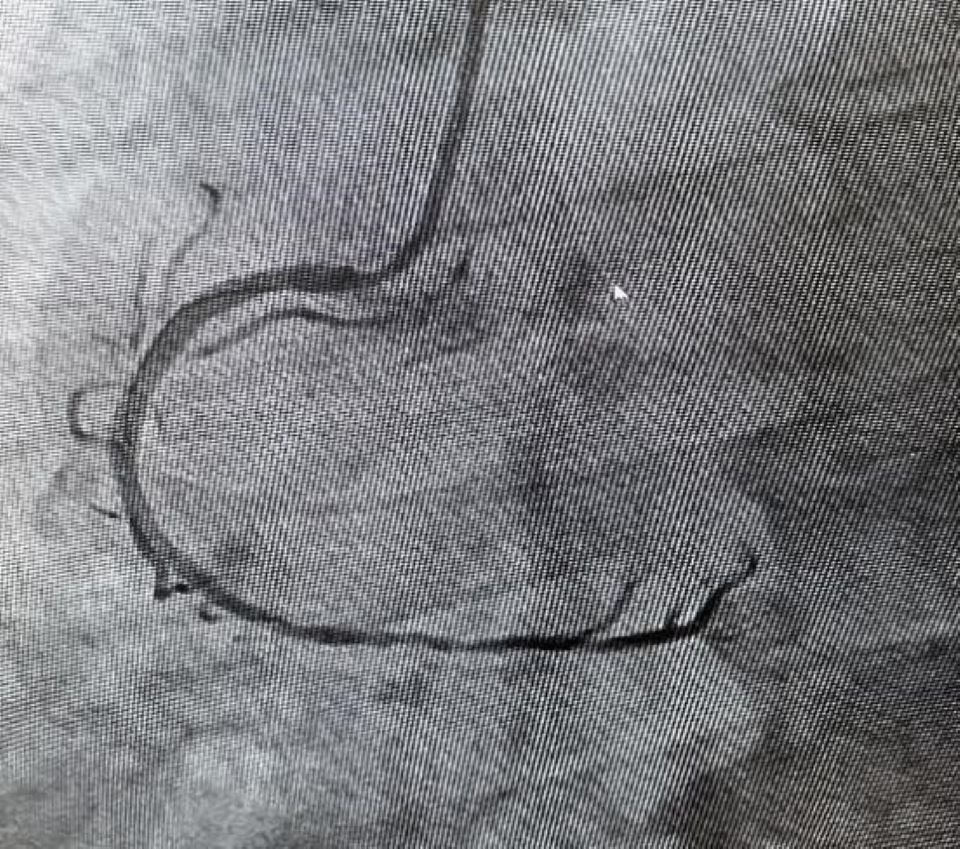

During the procedure, coronary angiography revealed severe lesions in all three coronary arteries. After discussion with local doctors, the CMT decided to treat the right coronary artery. From the selection of medical supplies and coronary puncture to the stent implantation, the CMT carefully explained key points and safety considerations. They guided the local doctors in successfully placing two stents in the right coronary artery, effectively relieving the blockage. The surgery was a complete success.